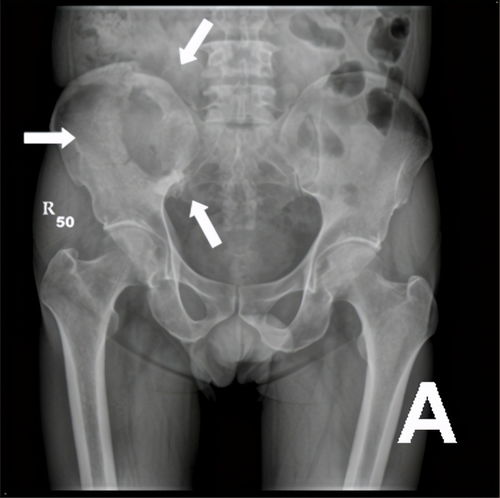

骨嗜酸性肉芽肿-骨溶骨性破坏,良性

骨嗜酸性肉芽肿——一种表现为溶骨性破坏的良性骨病探究 骨嗜酸性肉芽肿是一种以骨骼系统局限性溶骨性破坏为特征的良性病变,本质为朗格汉斯细胞的克隆性增生。本文系统阐述了该病的流行病学特征、病因假说、病理基础、临床表现与影像学特点,重点分析了其“良性溶骨性破坏”的独特性质,并综述了当前的诊断标准、鉴别诊断要点、个体化治疗策略及总体良好的预后,旨在深化临床及公众对这...